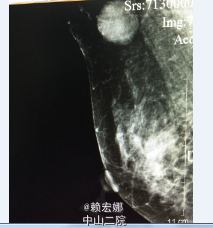

患者,女,2月前因发现右乳肿物

曾在局麻下行B超引导下右侧乳腺肿物穿刺活检术 +右侧腋窝肿物穿刺活检术,原发肿物:右乳12点钟乳晕旁见一大小为2.5*2.1cm的实性低回声团,右侧腋窝淋巴结3.5*1.9cm,术后病理:(右乳肿物、右腋窝肿物穿刺)乳腺浸润性导管癌,Ⅲ级。免疫组化:ER(-)、PR(-)、Her-2(3+)、Ki-67(+,40%)、P63(-)、E-cad(+)、Calponin(-)。

右侧乳腺癌诊断明确,予以TE新辅助化疗三次后,复查彩超:右乳12点钟乳晕旁见范围约1.4*0.9cm的实质性低回声团,边界不清,右乳10点钟方位见一大小为0.7*0.3cm的实性低回声团,边界清,形态规则,提示:1.右乳实性占位,多考虑乳腺Ca可能(较前次检查明显缩小);右乳实性低回声团,多考虑增生结节可能(BI-RADS Ⅱ类);双侧乳腺符合乳腺增生征象;2、双侧腋窝见淋巴结(右侧部分淋巴结淋巴门偏心)。患者经新辅助化疗后肿物明显缩小。患者完善相关检查,无明显手术禁忌症,遂在全麻下行右侧乳腺癌改良根治术+前哨淋巴结活检术,术后病理:1、(右侧乳腺浸润性导管癌癌灶剔除术后)残腔未见癌残留;2、乳腺及皮瓣四侧切缘,基底边缘及乳头未见癌浸润;3、(前哨、腋窝)淋巴结未见癌转移(0/3、0/14)。